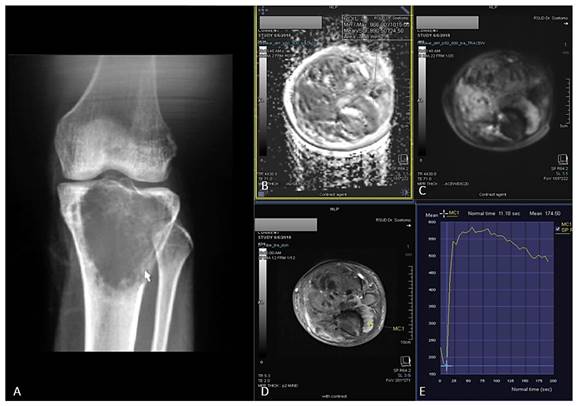

Figure 2

23 years-old man, with chondroblastic osteosarcoma histopathologically in proximal left tibia. X-ray left cruris AP and lateral projection (A) multiple osteolytic lesion in diaphysis of proximal left tibia with chondroid matrix and soft tissue bulging around it. Restricted diffusion on DWI and ADC map (B,C) with ADC value 1.245 x 10-3 mm2/s, on Dynamic Contrast Enhancement show early contrast enhancement followed by plateu phase /TIC type 3 (D,E) with the %slope result was 7,52 %/s.

In general, malignant tumor has much vascularity and narrow extravascular or interstitial space. Thus, it exhibited rapid and high contrast enhancement 2,25. Tucbilek et al (2004) stated that the steepest lope value accurately reflects tumor vascularization, the malignant soft tissue tumor showed early elevation signal intensity and steepest slope e.g. liposarcoma 28. Two cases of chondroblastic and osteoblastic OS with the presented of ADC value mapping and TIC on DCE were described on Figure 1 and Figure 2.